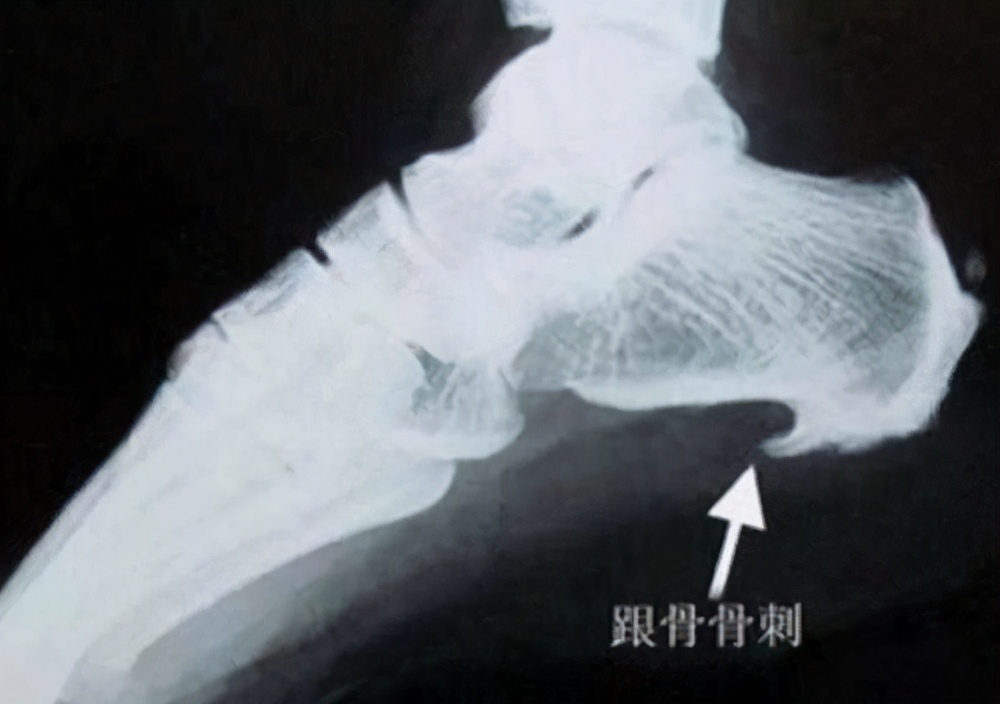

很多人觉得骨刺是脚后跟疼的主要原因,甚至认为“只有骨刺去除了,我的疼痛才会好”。骨刺是一种正常的生理退化现象,就如同人老了会长皱纹一样。只有当骨刺引起疼痛时才需要对症治疗。骨刺并不可怕,只要没有引起病理改变,就可以与人体和平共处。其实大多数脚后跟疼是由炎症引起的,即足底筋膜炎。跟骨骨刺是一种保护机制,却一直替足底筋膜炎背黑锅了。可是,我的脚又没破,怎么会有炎症呢?这里的炎症指的是「无菌性炎症」,多见于慢性劳损、运动损伤等,和我们日常认识的细菌感染不一样,所以头孢等抗菌素药物治疗无效。